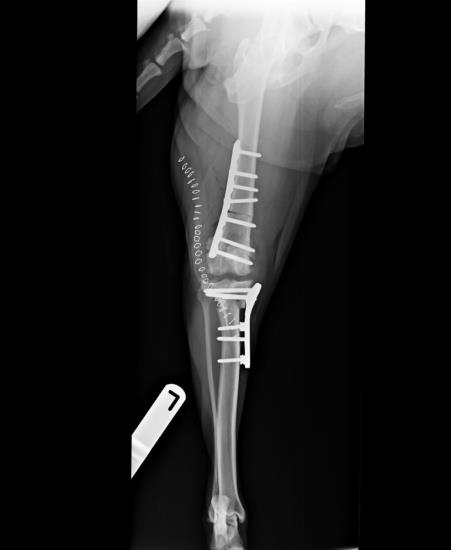

TPLO has been shown to be a robust and reliable procedure for dogs of all sizes. Most dogs are weight bearing well on the operated leg the day following surgery and benefit from the early limb use this allows. The procedure is designed to change the biomechanics of the stifle joint such that it neutralises cranial tibial thrust during the stance phase effectively doing away with the need for a cranial cruciate ligament. TPLO is suitable for dogs at every stage of cruciate disease from early partial tears, acute traumatic cruciate tears to chronic arthritic stifles. We expect 95% of dogs to have a good or excellent outcome following TPLO with a low rate of complications. A recent study by Krotscheck 2016 compared extracapsular suture, tibial tuberosity advancement and TPLO, using force plate assessment at 8 weeks, 6 months and 12 months. Whilst dogs having TTA had slightly better weight bearing at 8 weeks, TPLO was the only surgery able to return dogs to normal weight bearing at 6 and 12 months after surgery at both a walk and a trot. With this evidence we consider TPLO to be the best option for the treatment of cruciate disease in dogs.

Figure 1. Tibial plateau levelling osteotomy using a broad locking plate and screws in a 45kg Labrador